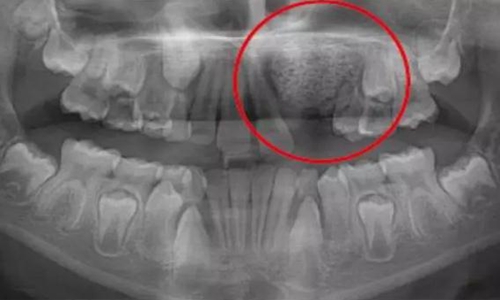

一名 23 區(qū)的9歲患者,在診所接受檢查時發(fā)現(xiàn)口內(nèi)中存在大范圍含牙囊腫[圖1]。由于上頜竇下沿出現(xiàn)大范圍突出,迫切需要接受囊腫去除手術(shù)[圖2和3]。

囊腫去除后的大量骨缺損[圖3]